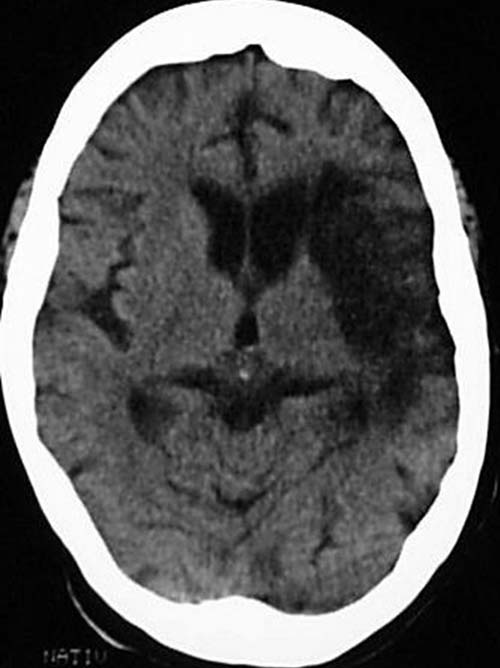

Patient, 60 Jahre alt, mit seit Jahren andauernder Halbseitenlähmung rechts.

CCT nativ (ohne Kontrastmittel).

Hypodense Darstellung des Mediastromgebietes li. und Substanzdefekt. E vacuo Erweiterung des linken Seitenventrikels.

Alter Mediainfarkt links (> 3 Monate).